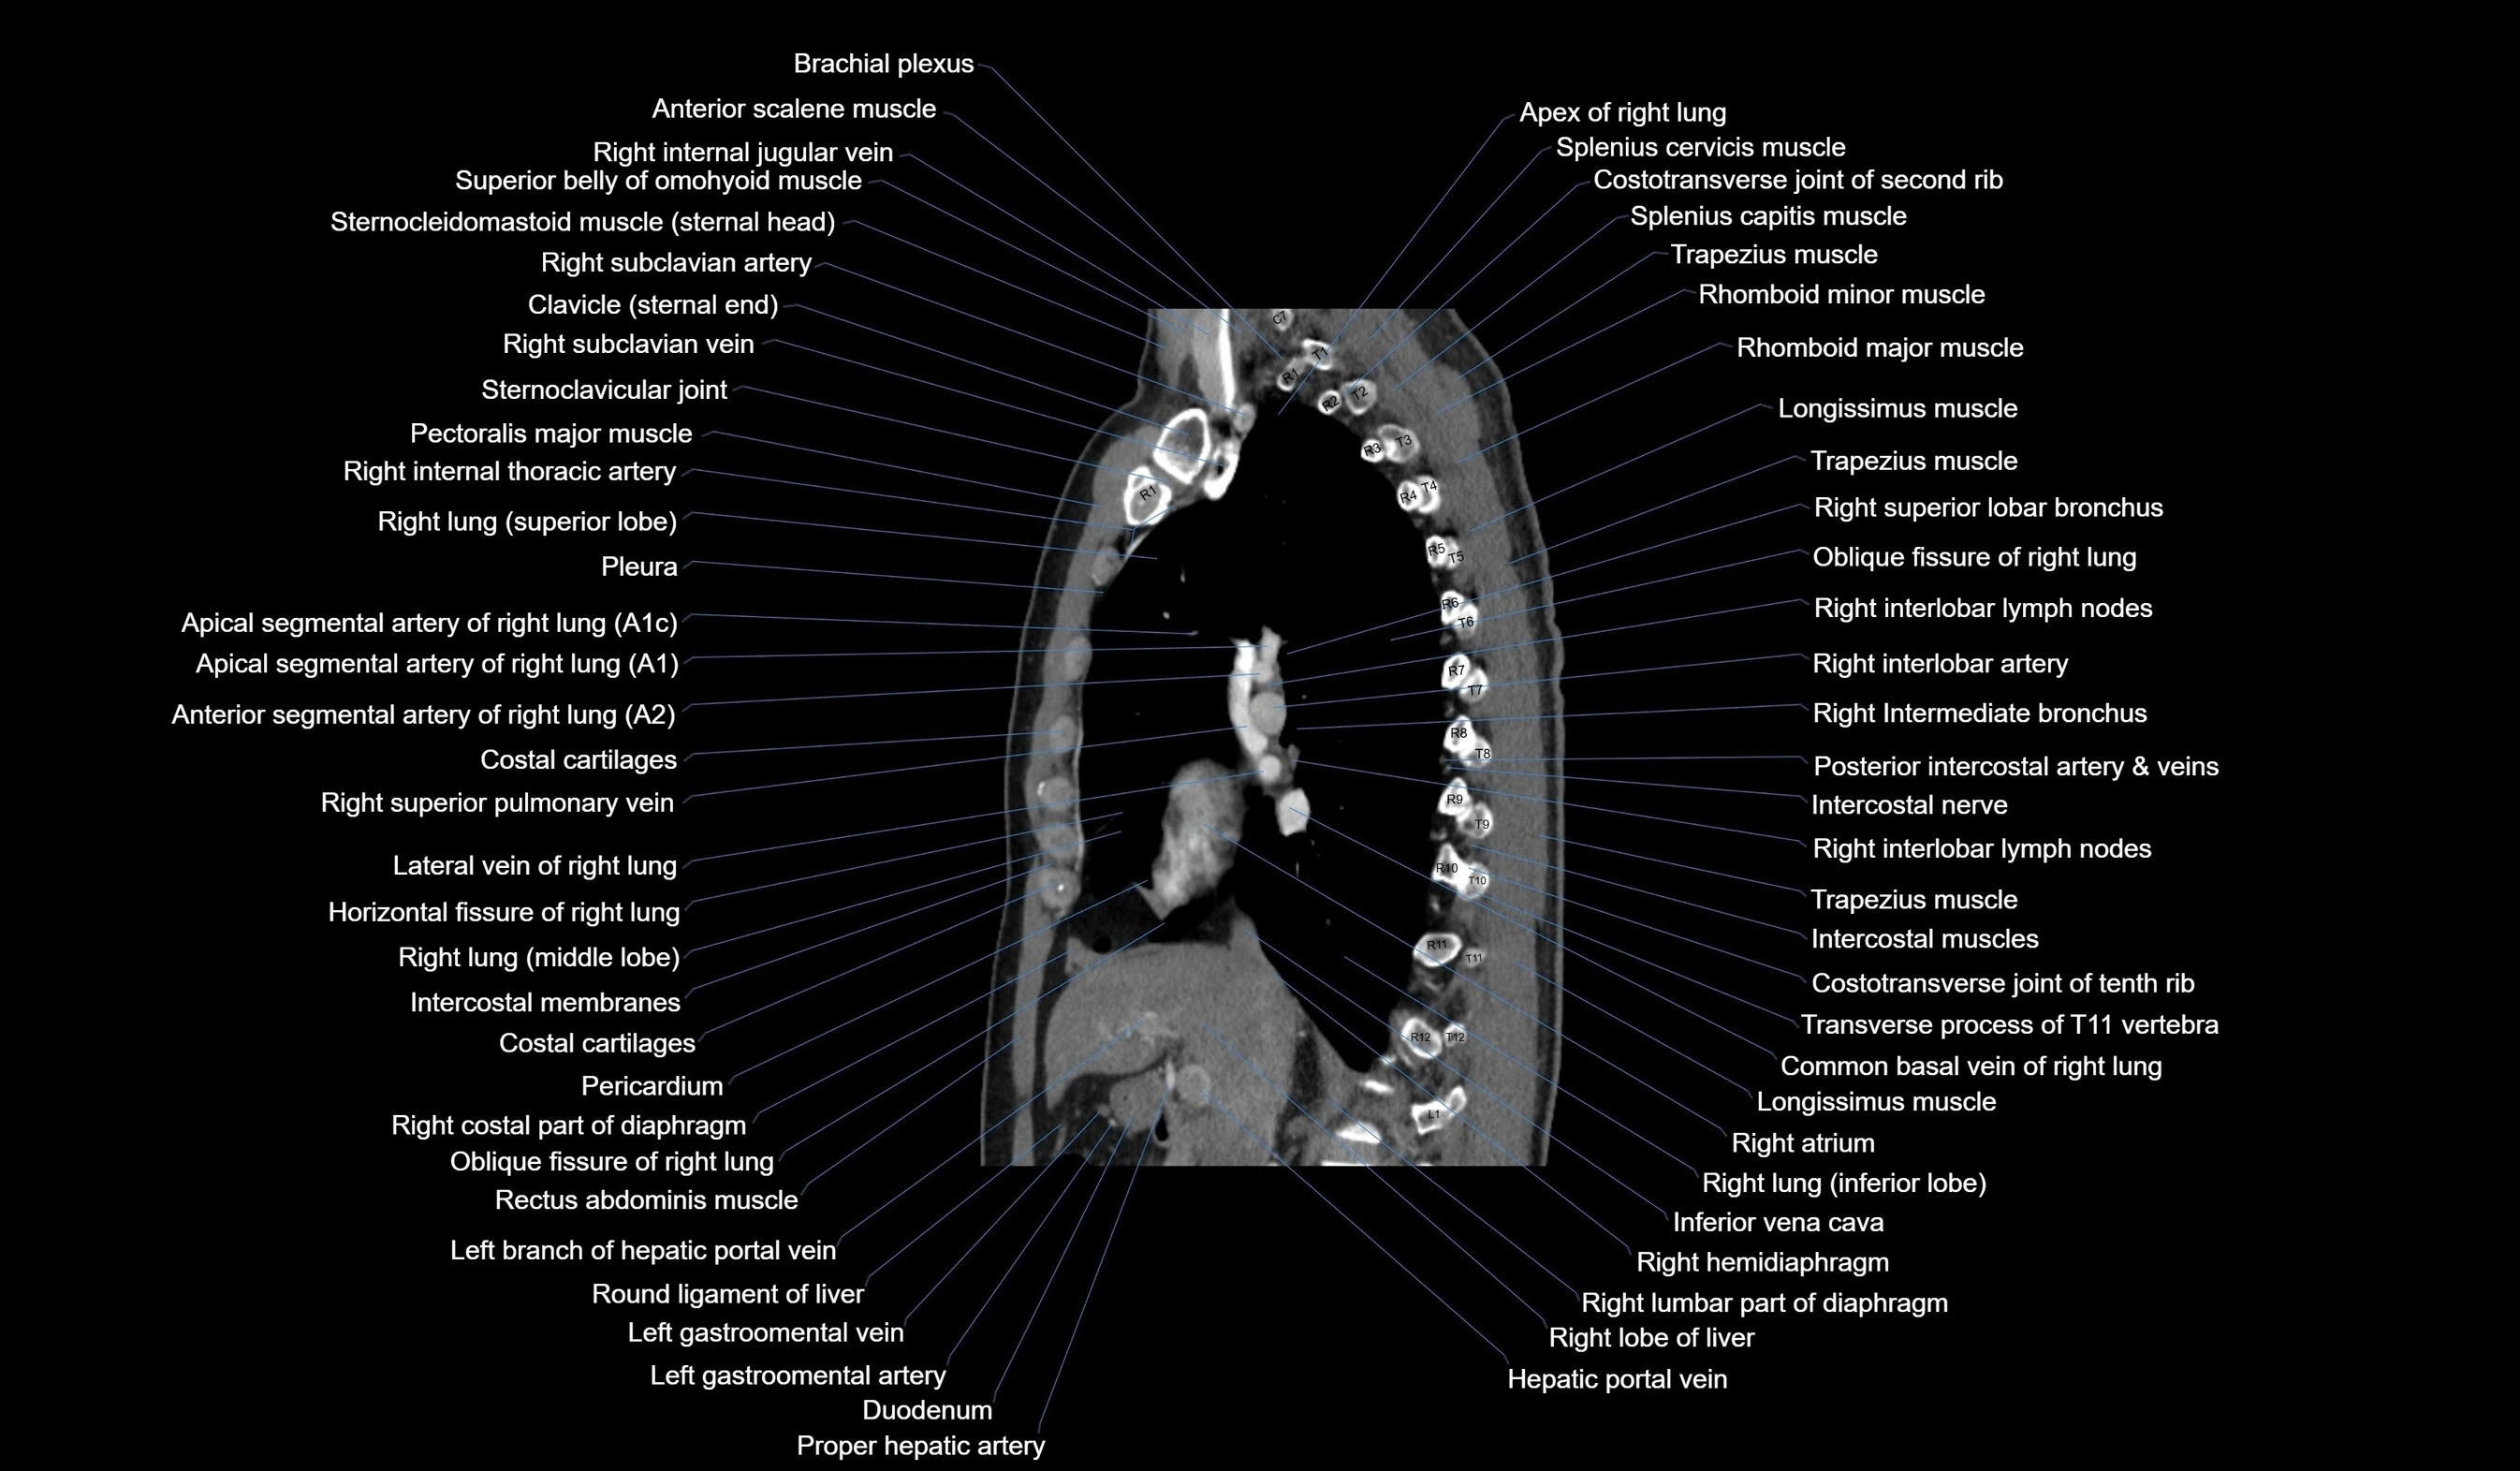

CT images